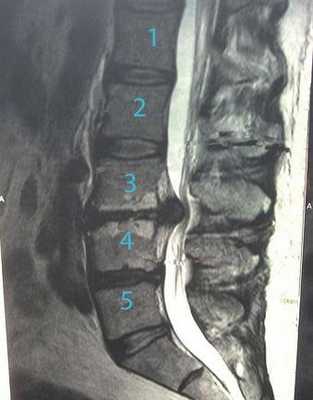

Грыжа поясничного отдела.

Что примечательно, основная доля из всех известных заболеваний спины приходится на пояснично-крестцовый отдел. Так, по данным некоторых медицинских источников, пациенты первично обращаются к врачу с жалобами на вертебральный синдром в пояснице примерно в 75% случаев, в шее - в 25%, в грудной области - в 5%. Главной причиной ощущения дискомфорта в хребтовых зонах является грыжа позвоночника или деформация позвоночного столба.